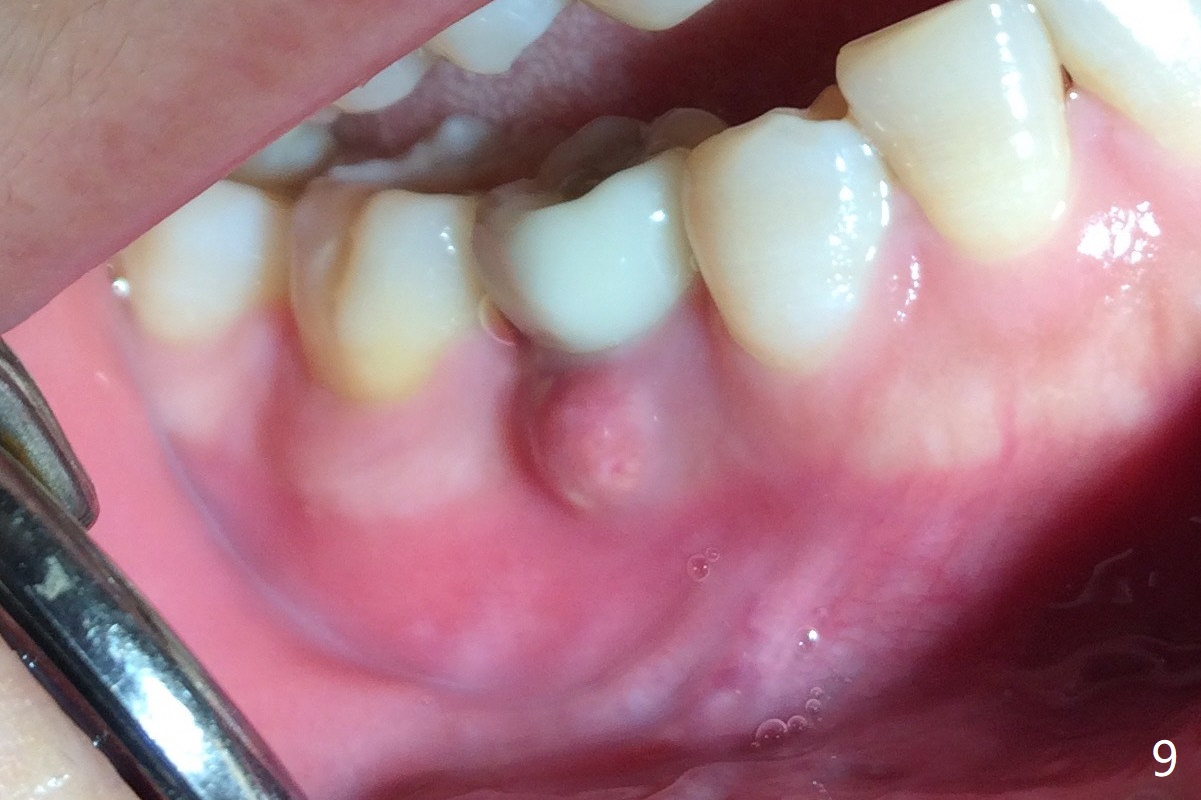

The lower 2nd primary molar has buccal furca lesion (Fig.1 *) with the thin buccal plate (Fig.2). Osteotomy is initiated in the sloped septum (Fig.3). After use of Magic Drill (MD) 3.3 mm for 13 mm and MD 3.8 mm for 11 mm, placement of a 4x11 mm IBS implant meets resistance because of the dense bone (Fig.4-6, red dashed line: Mental Loop) with final insertion torque >50 Ncm. After placement of a 6x4(3) mm abutment and autogenous bone in the remaining shallow sockets (Fig.6), a provisional is fabricated (Fig.7). Finally periodontal dressing is applied. Impression is taken 3 months postop (Fig.8). Buccal infection develops 2 weeks post cementation (Fig.9). When the crown/abutment is removed, there is no residual cement. The implant threads can be felt through the fistula. After soft tissue debridement and copious irrigation, Arestin is placed in the fistula. The latter disappears 15 days post debridement. The patient feels better and moves out of state. It appears that early periimplantitis develops because of the preexisting buccal furca lesion and failure to place the implant deep. The implant will be placed deep after loosening a little (since there is apical space (Fig.8 white line)) or removed, truncated at the apex and placed lower than the buccal crest.